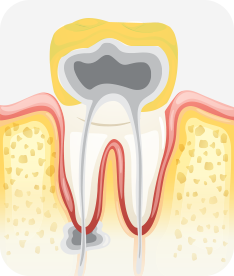

치아신경 염증

충치가 심해져 치아 뿌리까지 신경 염증이 발생함

신경치료 완료

소독된 신경관을 생체친화적인 재료로 충전한 후 보철치료를 함